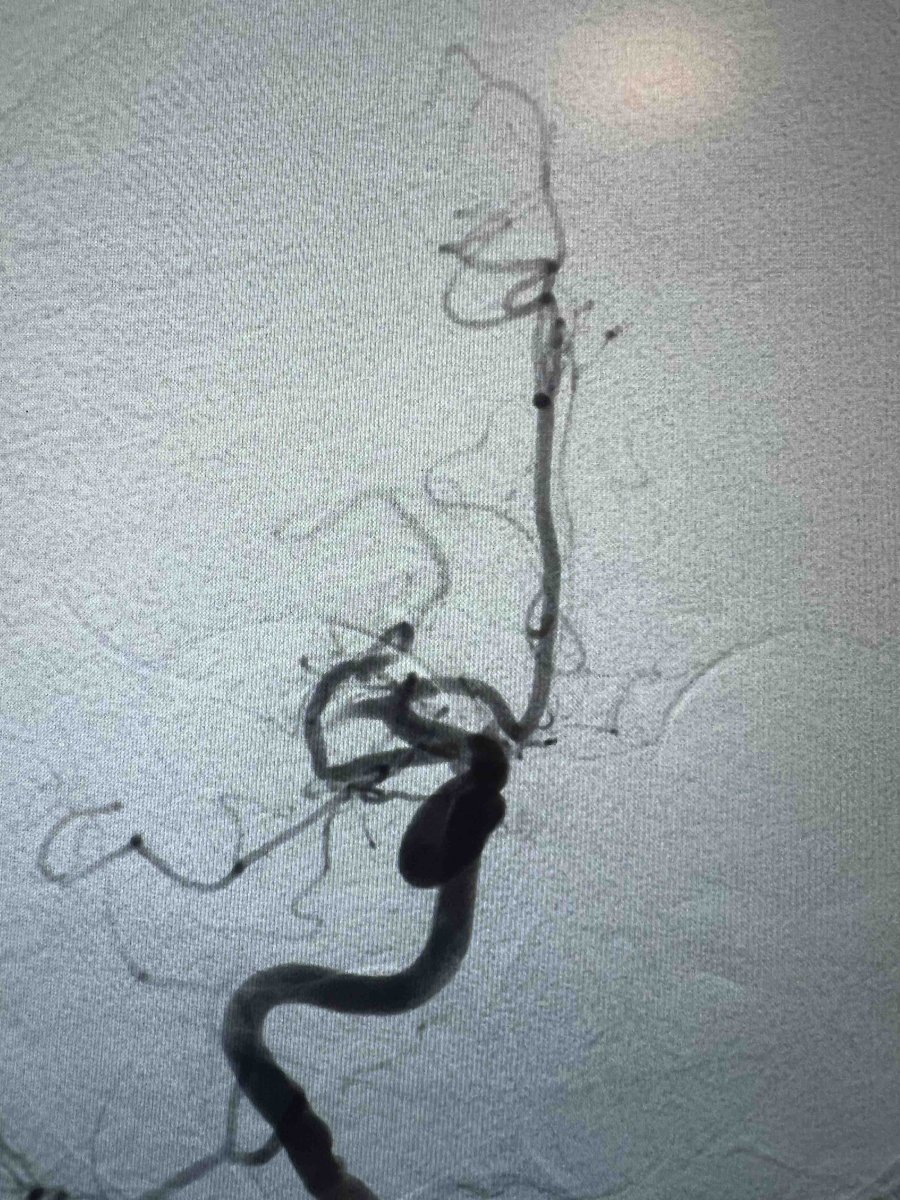

US HCPs: Check out this fantastic first pass result using RED 43 in left M2 from Dr. Amir Khan out of OC, CA! No clinical deficits or MRI infarct observed post thrombectomy. Thank you for sharing! #RED43 Rx only. Risk info: bit.ly/2BYj7Yj. Clinical results may vary.

PenNeuro's tweet image. US HCPs: Check out this fantastic first pass result using RED 43 in left M2 from Dr. Amir Khan out of OC, CA! No clinical deficits or MRI infarct observed post thrombectomy. Thank you for sharing! #RED43 Rx only. Risk info: bit.ly/2BYj7Yj. Clinical results may vary.